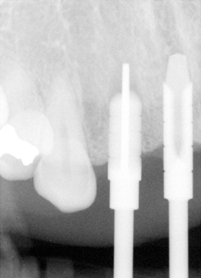

A 43 year-old lady has lost #7 and 8 due to caries for ~ 2 year. It appears that the ridge is wide (Fig.1). To place implants in ideal position, cone beam CT is planned. Models are mounted (Fig.2); diagnostic wax-up is finished (Fig.3). Drill sleeves (arrowheads in Fig.4; 10 mm long, 2.2 mm in diameter; Straumann) are placed lingual to the incisal (I) edges of the neighboring teeth. The position of drill sleeves is confirmed by CT: between the incisal edge and the cingulum (Fig.5). The cross sections at #7, 8 and 9 are shown in Fig. 6, 7 and 8, respectively. However, the long axis of the sleeve (S) or the natural tooth #9 is not aligned with that of the alveolar ridge. This orientation is good from prosthetic viewpoint, but we cannot place a long or wide implant. The lateral view of the three-dimensional image shows that the long axis of the crown (C) of #9 is not in line with that of its root/ridge (R, Fig.9). It appears that the trajectory of an implant should be not decided by wax-up, but should be adjusted to accommodate the morphology of the alveolar ridge. In all, the drill sleeve (S) should be moved and tilted more labially to place the longest and largest implant.